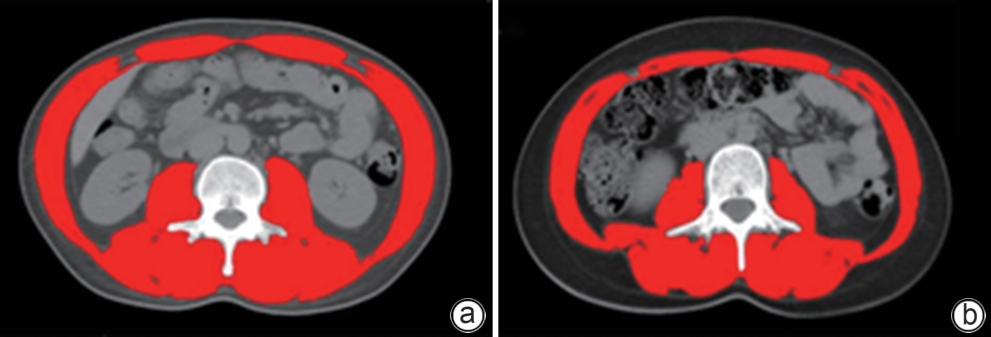

Establishment and validation of a risk prediction model for 90-day mortality in patients with acute-on-chronic liver failure based on sarcopenia

Huina CHEN, Ming KONG, Siqi ZHANG, Manman XU, Yu CHEN, Zhongping DUAN

2025, 41(6): 1135-1142. DOI: 10.12449/JCH250620

Abstract(1024) HTML (296) PDF (2616KB)(62)

Abstract:

Objective  To establish and validate a new prediction model for the risk of death in patients with acute-on-chronic liver failure (ACLF) based on sarcopenia and other clinical indicators, and to improve the accuracy of prognostic assessment for ACLF patients.  Methods  A total of 380 patients with ACLF who were admitted to Beijing YouAn Hospital, Capital Medical University, from January 2019 to January 2022 were enrolled, and they were divided into training group with 228 patients and testing group with 152 patients in a ratio of 6∶4 using the stratified random sampling method. For the training group, CT images were used to measure the cross-sectional area of the skeletal muscle at the third lumbar vertebra (L3), and L3 skeletal muscle index (L3-SMI) was calculated. Sarcopenia was diagnosed based on the previously established L3-SMI reference values for healthy adults in northern China. Univariate and multivariable Cox regression analyses were used to establish a sarcopenia-ACLF model which integrated sarcopenia and clinical risk factors, and a nomogram was developed for presentation. The area under the ROC curve (AUC) was used to assess the predictive performance of the model, the calibration curve was used to assess the degree of calibration, and a decision curve analysis was used to investigate the clinical application value of the model. The independent-samples t test or the Mann-Whitney U test was used for comparison of continuous data between two groups, and the chi-square test was used for comparison of categorical data between two groups. The Kaplan-Meier method was used to plot survival curves, and the Log-rank test was used for comparison between groups. The DeLong test was used for comparison of AUC between different models.  Results  The multivariate Cox regression analysis showed that sarcopenia (hazard ratio [HR]=1.962, 95% confidence interval [CI]: 1.185‍ ‍—‍ ‍3.250, P=0.009), total bilirubin (HR=1.003, 95%CI: 1.002‍ ‍—‍ ‍1.005, P<0.001), international normalized ratio (HR=1.997, 95%CI: 1.674‍ ‍—‍ ‍2.382, P<0.001), and lactic acid (HR=1.382, 95%CI: 1.170‍ ‍—‍ ‍1.632, P<0.001) were included in the sarcopenia-ACLF model. In the training cohort, the sarcopenia-ACLF model had a larger AUC than MELD-Na score in predicting 90-day mortality in patients with ACLF (0.80 vs 0.73, Z=1.97, P=0.049). In the test cohort, the sarcopenia-ACLF model had a significantly larger AUC than MELD score (0.79 vs 0.69, Z=2.70, P=0.007) and MELD-Na score (0.79 vs 0.68, Z=2.92, P=0.004). The calibration curve showed that the model had good calibration ability, with a relatively good consistency between the predicted risk of mortality and the observed results. The DCA results showed that within a reasonable range of threshold probabilities, the sarcopenia-ACLF model showed a greater net benefit than MELD and MELD-Na scores in both the training cohort and the test cohort.  Conclusion  The sarcopenia-ACLF model developed in this study provides a more accurate tool for predicting the risk of 90-day mortality in ACLF patients, which provides support for clinical decision-making and helps to optimize treatment strategies.